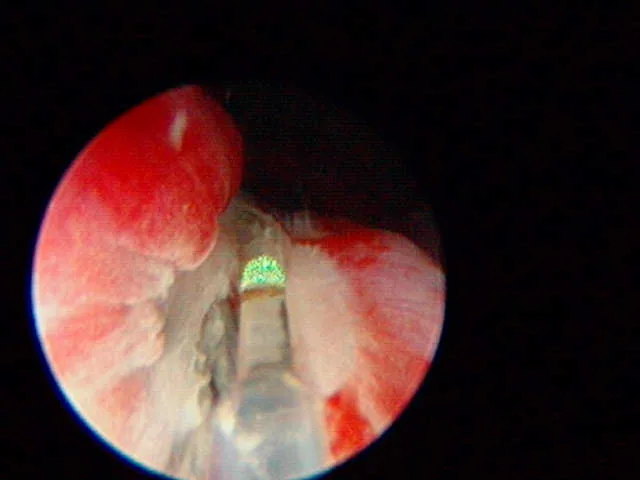

A

The plastic stent has been placed in the EU and the laser (green tip) is ablating the tissue over the stent.